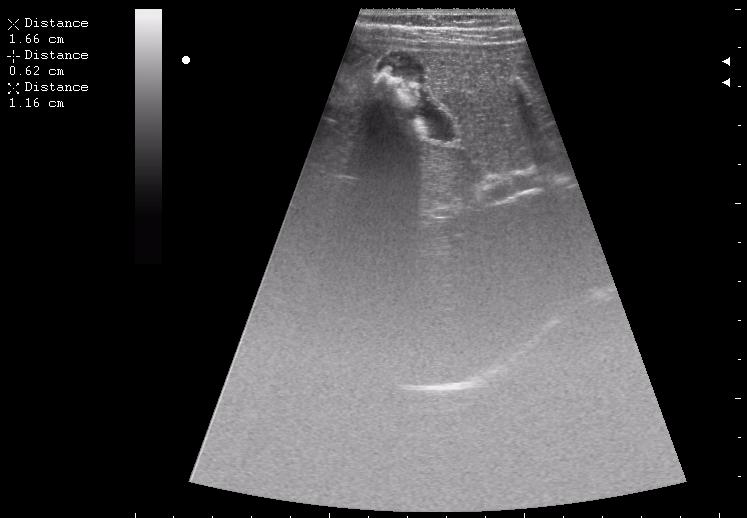

>желтой стрелкой - это левый надпочечник?

Похоже.

Он обычно располагается больше кнутри от верхнего полюса почки и может досигать ее ворот.

Надежнее визуализировать ЛН из позиции, которую я показывал в известной Вам теме.